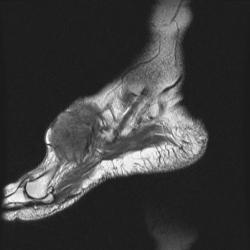

сагиттальная Т2

На серии МР-томограмм получены изображения правого голеностопного сустава.

На тыльной поверхности правой стопы, непосредственно под кожей в области таранной, ладьевидной, клиновидных и оснований от первой до третьей плюсневых костей определяется патологическое образование (тофусы), с распространением на медиальную поверхность стопы, образование неоднородной структуры и МР-сигнала, умеренно гиперинтенсивное на Т1 ВИ, гипоинтенсивное на Т2 ВИ и неоднородного на FAT SAT ИП. Размеры образования 35 х 65 х 40 мм. На постконтрастных изображениях отмечается значительное диффузное усилением интенсивности МР-сигнала от образования. Аналогичные по МР-характеристикам образования, меньших размеров выявляются в левой стопе.

Со стороны костной системы определяются: единичные костно-хрящевые дефекты со склерозом по периферии, диаметром до 3 мм, располагающиеся в субхондральных отделах в области суставных концов большеберцовой и малоберцовой костей, в области прикрепления длинной подошвенной связки к подошвенной поверхности пяточной кости. Множественные дефекты диаметром до 9 мм расположены в области смежных поверхностей ладьевидной и клиновидных костей, некоторые кистовидные дефекты вскрылись в мягкие ткани.

В пяточной кости правой стопы, определяется округлая зона повышенной интенсиновсти МР-сигнала на всех импульсных последовательностях в области блока малоберцовой кости, размерами 7 х 8 мм.

Суставные поверхности уплощены, суставные щели резко сужены, местами определяются краевые костные разрастания.